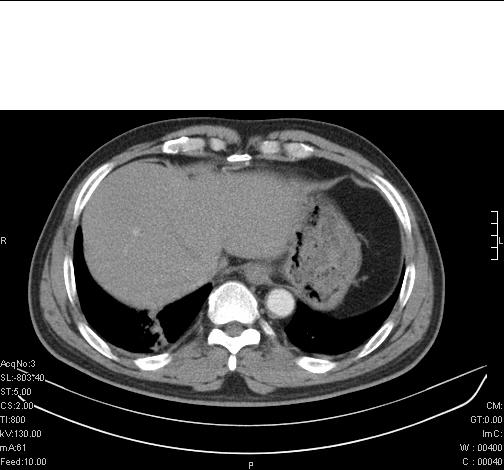

前几天,发了患者的平扫片,患者抗炎一周后增强扫描。右中叶病灶吸收明显,但下叶病灶未见明显吸收。右肺门可见结节影,看来凶多吉少

右肺下叶支气管管腔狭窄,管壁增厚,右下肺见斑片状高密度影,考虑右侧肺门中心肺癌伴阻塞性肺炎

右肺下叶支气管壁明显增厚,考虑癌症并阻塞性炎症、肺门淋巴结肿大

考虑右肺癌并阻塞性炎症、肺门淋巴结肿大

右肺下叶支气管壁不规则增厚,右肺下叶有斑片状影分布。考虑右肺中央型肺癌伴右肺下叶阻塞性改变。建议支纤镜检查。平扫比增强较好显示了病变情况。

右主支气管狭窄,管壁增厚。考虑右中心性肺ca伴阻塞性肺炎。

既然抗炎治疗有效,可继续治疗;右肺下叶支气管管腔狭窄,管壁增厚,右下肺见斑片状高密度影,右侧主支气管后见结节影(淋巴结?),肺癌不能排出。